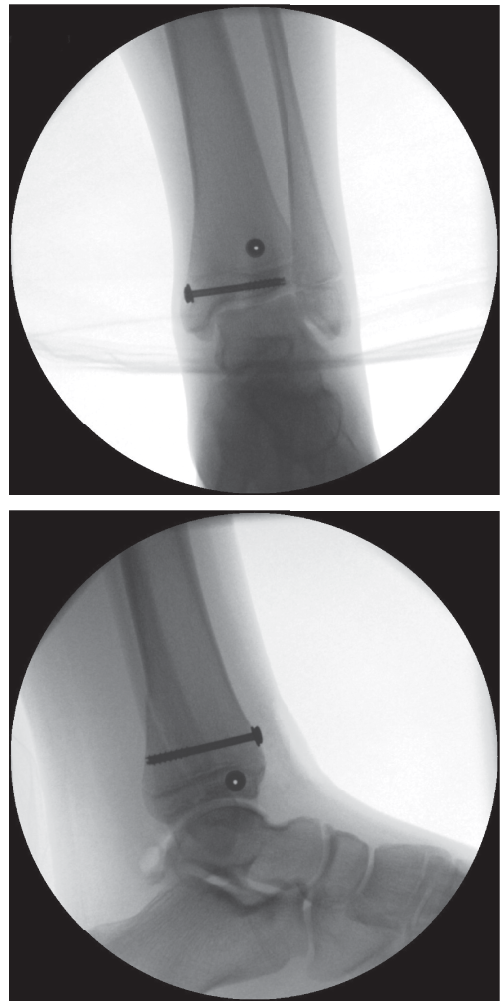

![Image](/media/upload/c3e99d07-aebc-4006-be81-94800f827e35.png)

* Caption: Post-operative radiograph demonstrating appropriate fixation of a Tillaux fracture with two cannulated screws. Note the trajectory of the screws, aiming for stable interfragmentary compression while minimizing physeal disturbance.